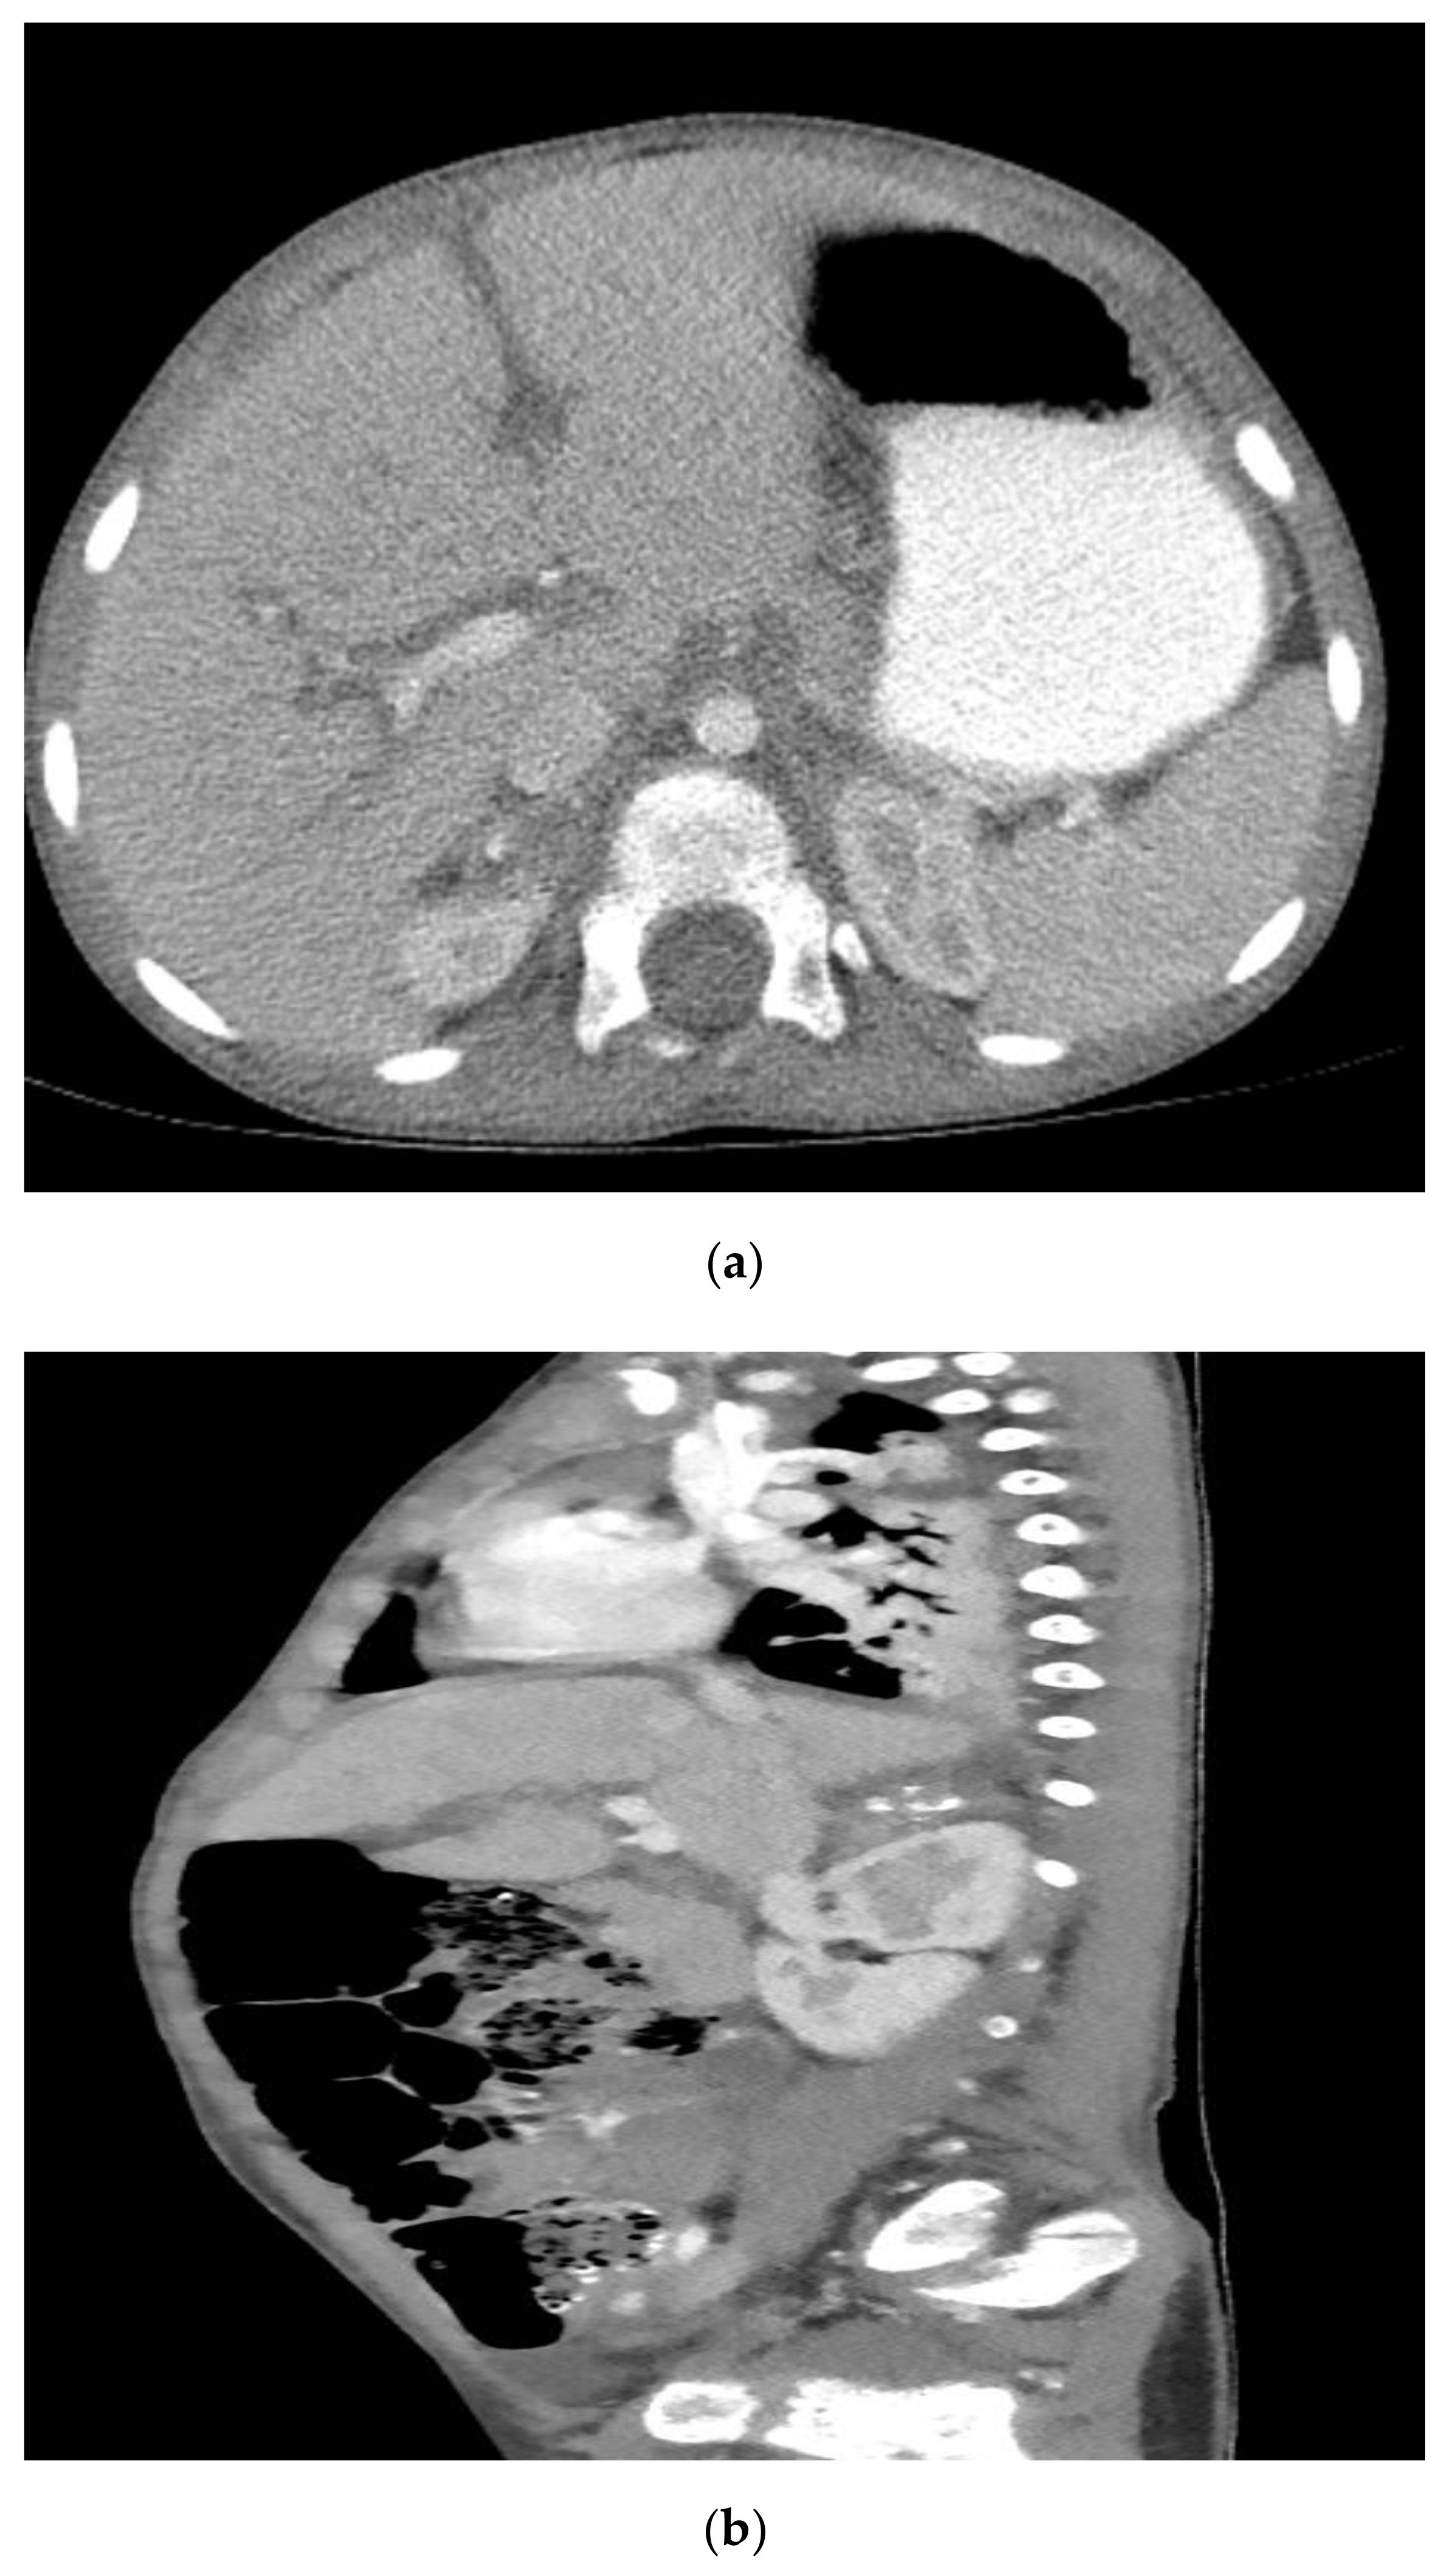

2. Case Report